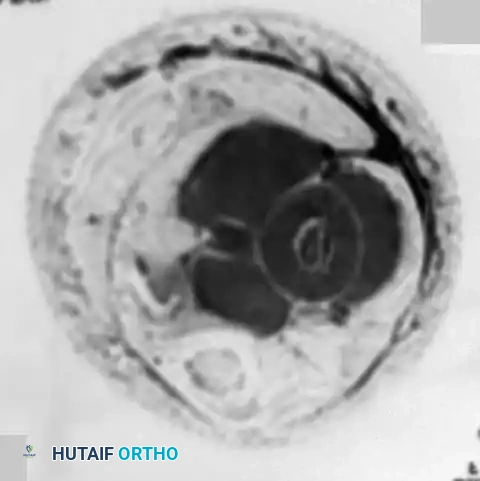

Fig. 22-9 A and B, Anteroposterior and lateral radiographs of the left fibula of a 7-year-old girl with Ewing sarcoma. Involvement of a large portion of the bone (or even the entire bone) is typical of Ewing sarcoma. C, MRI shows a large soft-tissue mass. D, Typical microscopic appearance of Ewing sarcoma.

- Magnetic Resonance Imaging (MRI): An MRI of the entire involved bone is mandatory. While "skip" metastases (common in osteosarcoma) are not a recognized feature of Ewing sarcoma, it is highly common for a massive portion of the marrow cavity—or the entire bone—to be involved. MRI is unparalleled in defining the intramedullary extent and delineating the extraosseous soft-tissue mass, which is often disproportionately large compared to the degree of cortical destruction.